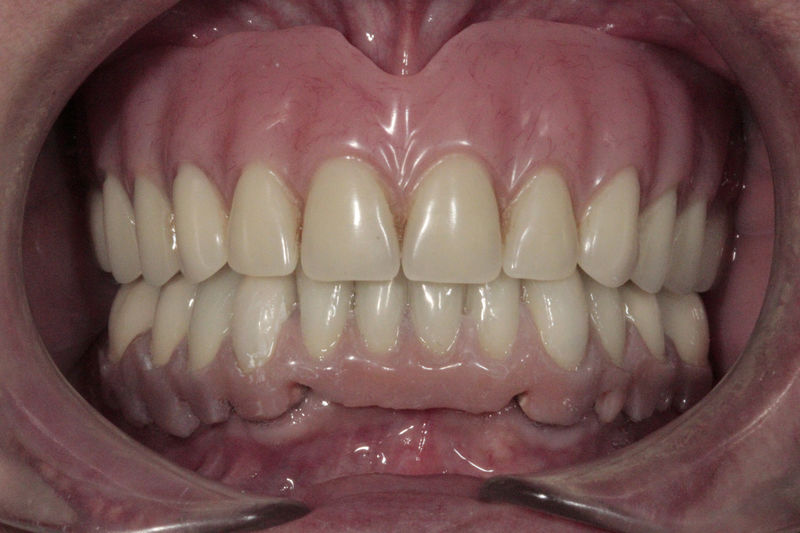

Disciplina fundamental de la Odontología enfocada en el diagnóstico, prevención y tratamiento restaurador de las piezas dentales que han sufrido daños. Su objetivo principal es devolver al diente su equilibrio biológico, funcional y estético cuando su integridad ha sido alterada. Resinas directas, incrustaciones, coronas.

Amplia gama de tratamientos para mejorar la apariencia de la sonrisa, corrigiendo el color, la forma, el tamaño, la alineación y la posición de los dientes. Los procedimientos más comunes y solicitados incluyen el blanqueamiento dental, las carillas y coronas, así como las resinas.

Restauraciones fabricadas en el laboratorio con materiales estéticos, los cuales cubren de manera total dientes anteriores y posteriores. Se utilizan primariamente para restaurar dientes con caries, fracturas y/o defectos amplios, así como soportes de puentes. Para poder enviar el caso al laboratorio se toman impresiones utilizando materiales de impresión o técnicas modernas digitales.